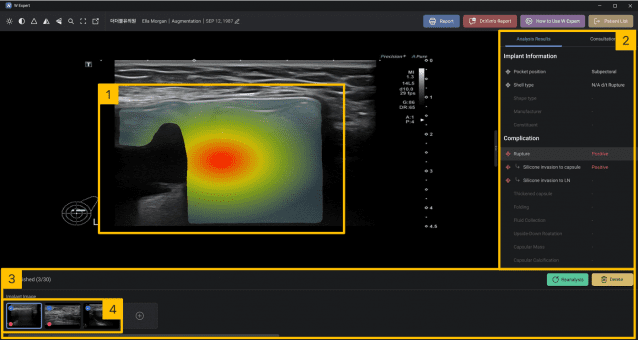

하지만 골드 스탠다드인 MRI는 고비용과 접근성 문제로 정기 검진에 활용하기 어렵다는 한계가 있다. 더블유 엑스퍼트는 바로 이 지점을 파고든다. 세계 최초 초음파 이미지만으로 보형물 표면 유형을 구분하는 기술을 확보하면서다. 증상이 없는 실리콘 유방 보형물 파열 여부도 진단할 수 있다.

더블유 엑스퍼트는 국내 다기관 임상시험에서 정확도 96%, 민감도 93%를 기록했다. 김 대표는 "한국은 다양한 국가 유방 보형물이 수입되는 시장이라 데이터 다양성 측면에서 미국이나 유럽 의사들이 개발한 AI보다 월등한 경쟁 우위를 갖는다"고 말했다.